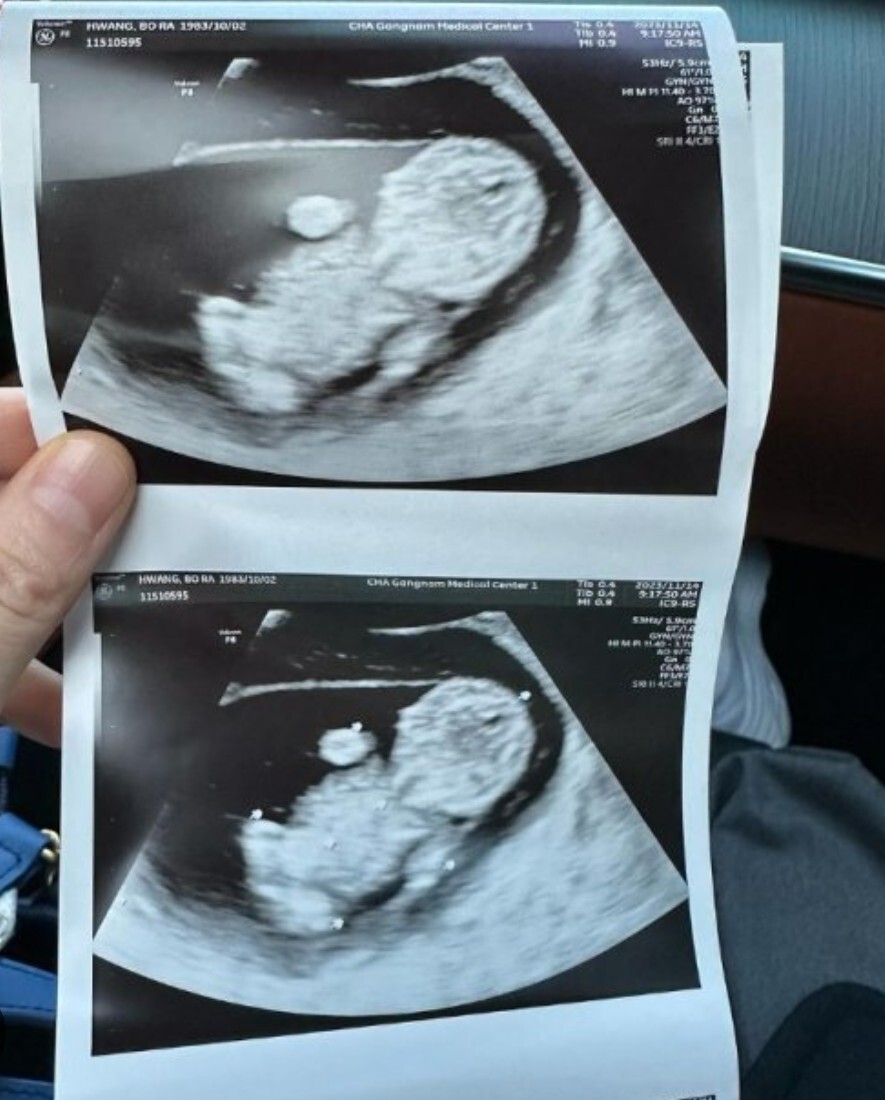

황보라는 최근 2023년 11월에 임신소식을 알리기도 했는데요. 황보라는 임신가능성이 1%였지만 임신에 성공하였고, 태명은 오덕이라고 합니다.